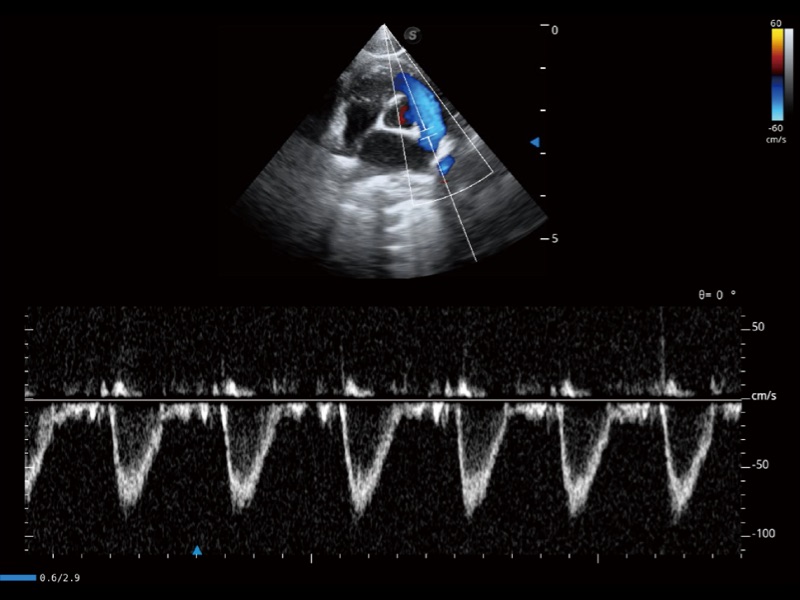

通過360度任意調(diào)節(jié)3條M型取樣線,在同一心動周期上觀察心臟不同位置的運(yùn)動曲線,得到準(zhǔn)確的心功能測量數(shù)據(jù),有效評估心肌運(yùn)動及左心室功能。